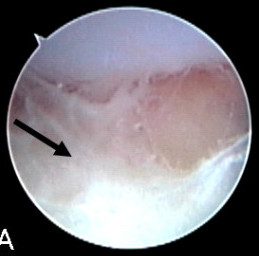

Septic arthritis as seen during arthroscopy[1]